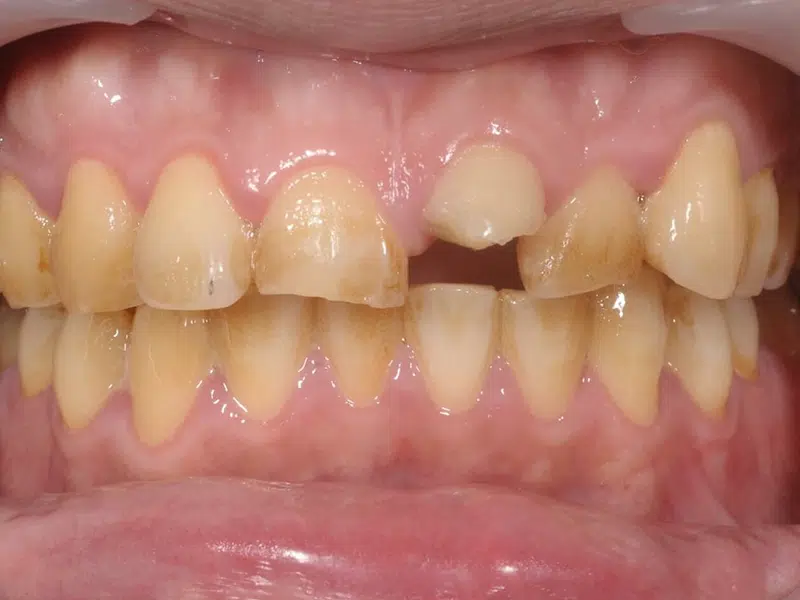

左邊是拔牙前的樣子,可以發現側門牙因為牙周病的關係,外側有腫脹的膿包。這時候可以預料的是拔牙後會有嚴重的軟硬組織不足的問題,所以先利用矯正的方式將明顯下墜及外偏的正中門牙移動到較正確的位置,並將側門牙往下拉增加軟組織的量來減少將來植牙手術時的困難度。右邊圖為植牙完成後,可以發現由於有補足軟硬組織缺失的部分,所以牙齒的黑暗三角並不明顯,跟周圍的牙齒外觀也差異不大。